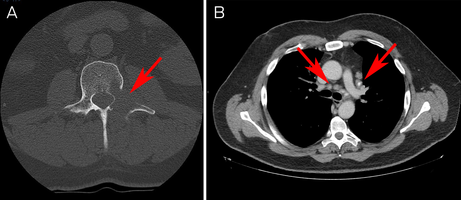

A computed tomography scan revealed a lytic lesion in the left L2 pedicle, mediastinal and hilar lymphadenopathy, and scattered pulmonary nodules concerning for malignancy (Box 1). There were also ground glass and tree‐in‐bud opacities in the right lower lobe suggesting inflammatory change.

Box 1 – (A) Axial section computed tomography (CT) scan of lytic lesion in left L2 pedicle. (B) Axial section CT chest scan showing mediastinal lymphadenopathy